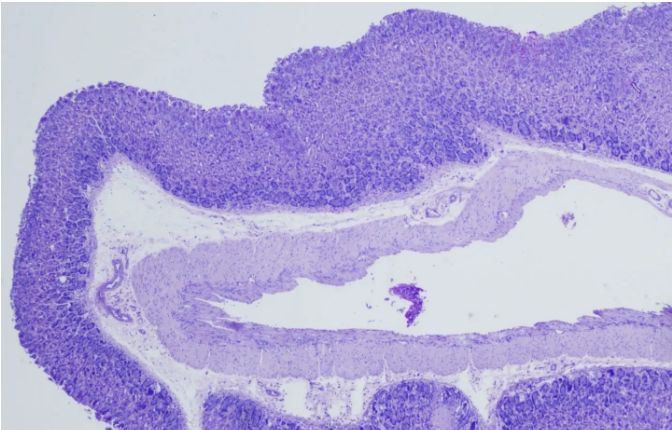

PAS染色結(jié)果解讀由普拉特澤生物給大家解答與分享,PAS染色(過碘酸雪夫染色)是一種重要的組織化學(xué)染色方法,廣泛應(yīng)用于病理診斷和科研實(shí)驗(yàn)。通過特定的化學(xué)反應(yīng),使組織中的多糖類物質(zhì)呈現(xiàn)出特殊的顏色,從而揭示其結(jié)構(gòu)和功能狀態(tài)。普拉特澤生物組織染色檢測平臺可承接各種病理染色外包服務(wù),包括HE染色

、油紅O染色、Masson染色等實(shí)驗(yàn)外包服務(wù),本文將詳細(xì)解讀PAS染色的結(jié)果,幫助科研小白更好地理解這一技術(shù)及其應(yīng)用。

首先,我們需要了解PAS染色的基本原理——過碘酸能夠氧化組織中的多糖類物質(zhì),使其形成醛基或酮基。隨后,雪夫試劑與這些醛基或酮基發(fā)生反應(yīng),生成不溶于水的有色化合物,從而在顯微鏡下呈現(xiàn)出特定的顏色。這種顏色反應(yīng)不僅具有高度的特異性,而且敏感性也很高,能夠準(zhǔn)確反映組織中多糖類物質(zhì)的分布和含量。

在解讀PAS染色結(jié)果時,我們需要關(guān)注以下幾個方面:

一、染色強(qiáng)度和分布

染色強(qiáng)度的深淺可以反映組織中多糖類物質(zhì)的含量。一般來說,染色越深,說明多糖類物質(zhì)含量越高;反之,染色越淺,則含量越低。同時,我們還需觀察染色的分布情況,以了解多糖類物質(zhì)在組織中的具體位置和形態(tài)。

二、細(xì)胞類型和結(jié)構(gòu)

PAS染色不僅可以顯示多糖類物質(zhì),還可以揭示細(xì)胞的類型和結(jié)構(gòu)。例如,在某些病理狀態(tài)下,某些細(xì)胞可能會過度分泌多糖類物質(zhì),導(dǎo)致染色結(jié)果異常。通過觀察這些細(xì)胞的形態(tài)和分布,我們可以進(jìn)一步了解疾病的發(fā)病機(jī)制和進(jìn)展過程。